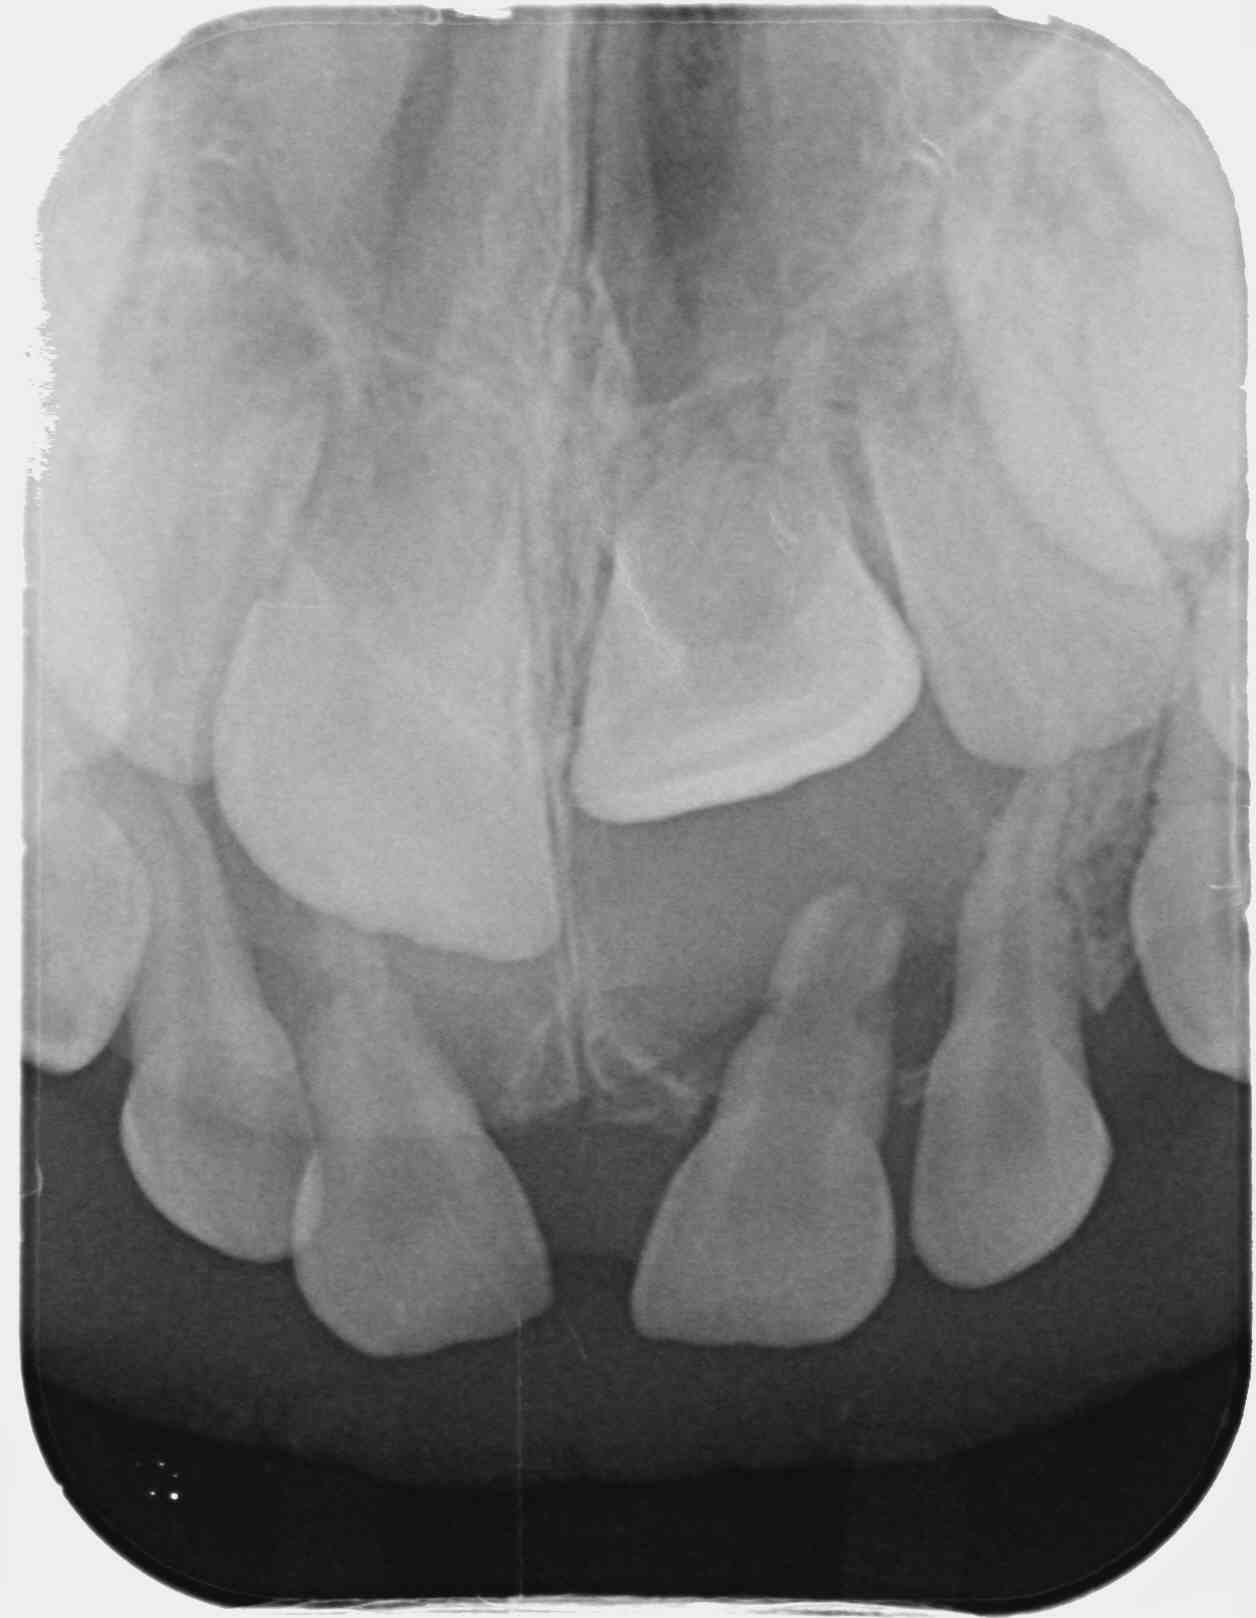

Garçon de 2 ans 11 mois, chute sur la face, peu de douleur, pas de mobilité, saignement sillon de 51.

Je ne vois rien de particulier à la radio.

Diagnostic de concussion je pense,

Il faudrait l'avis d'un pédo, mais en ce qui me concerne dans ce cas je fais une simple surveillance tous les 6 mois, y compris radiographique. Ce genre de trauma est extrêmement fréquent, les minéralisations ou nécrose des incisives lactéales consécutives sont aussi forcément très fréquentes. Les complications sont rares car la nature est plutôt bien faite sur ce coup là. La complication la plus évidente est un réveil infectieux aigu ou l'apparition d'une parulie (fistule) à l'apex, la plus vicieuse est la formation d'un granulome/kyste sans aucun symptôme clinique, avec déviation du germe de la centrale, indiquant l'avulsion de la dent lactéale concernée. Vu une fois en 12 ans.

Trauma à 2 ans, rvg à l'âge de 3 ans puis 5 ans (avulsion indiquée) puis à 7 ans.